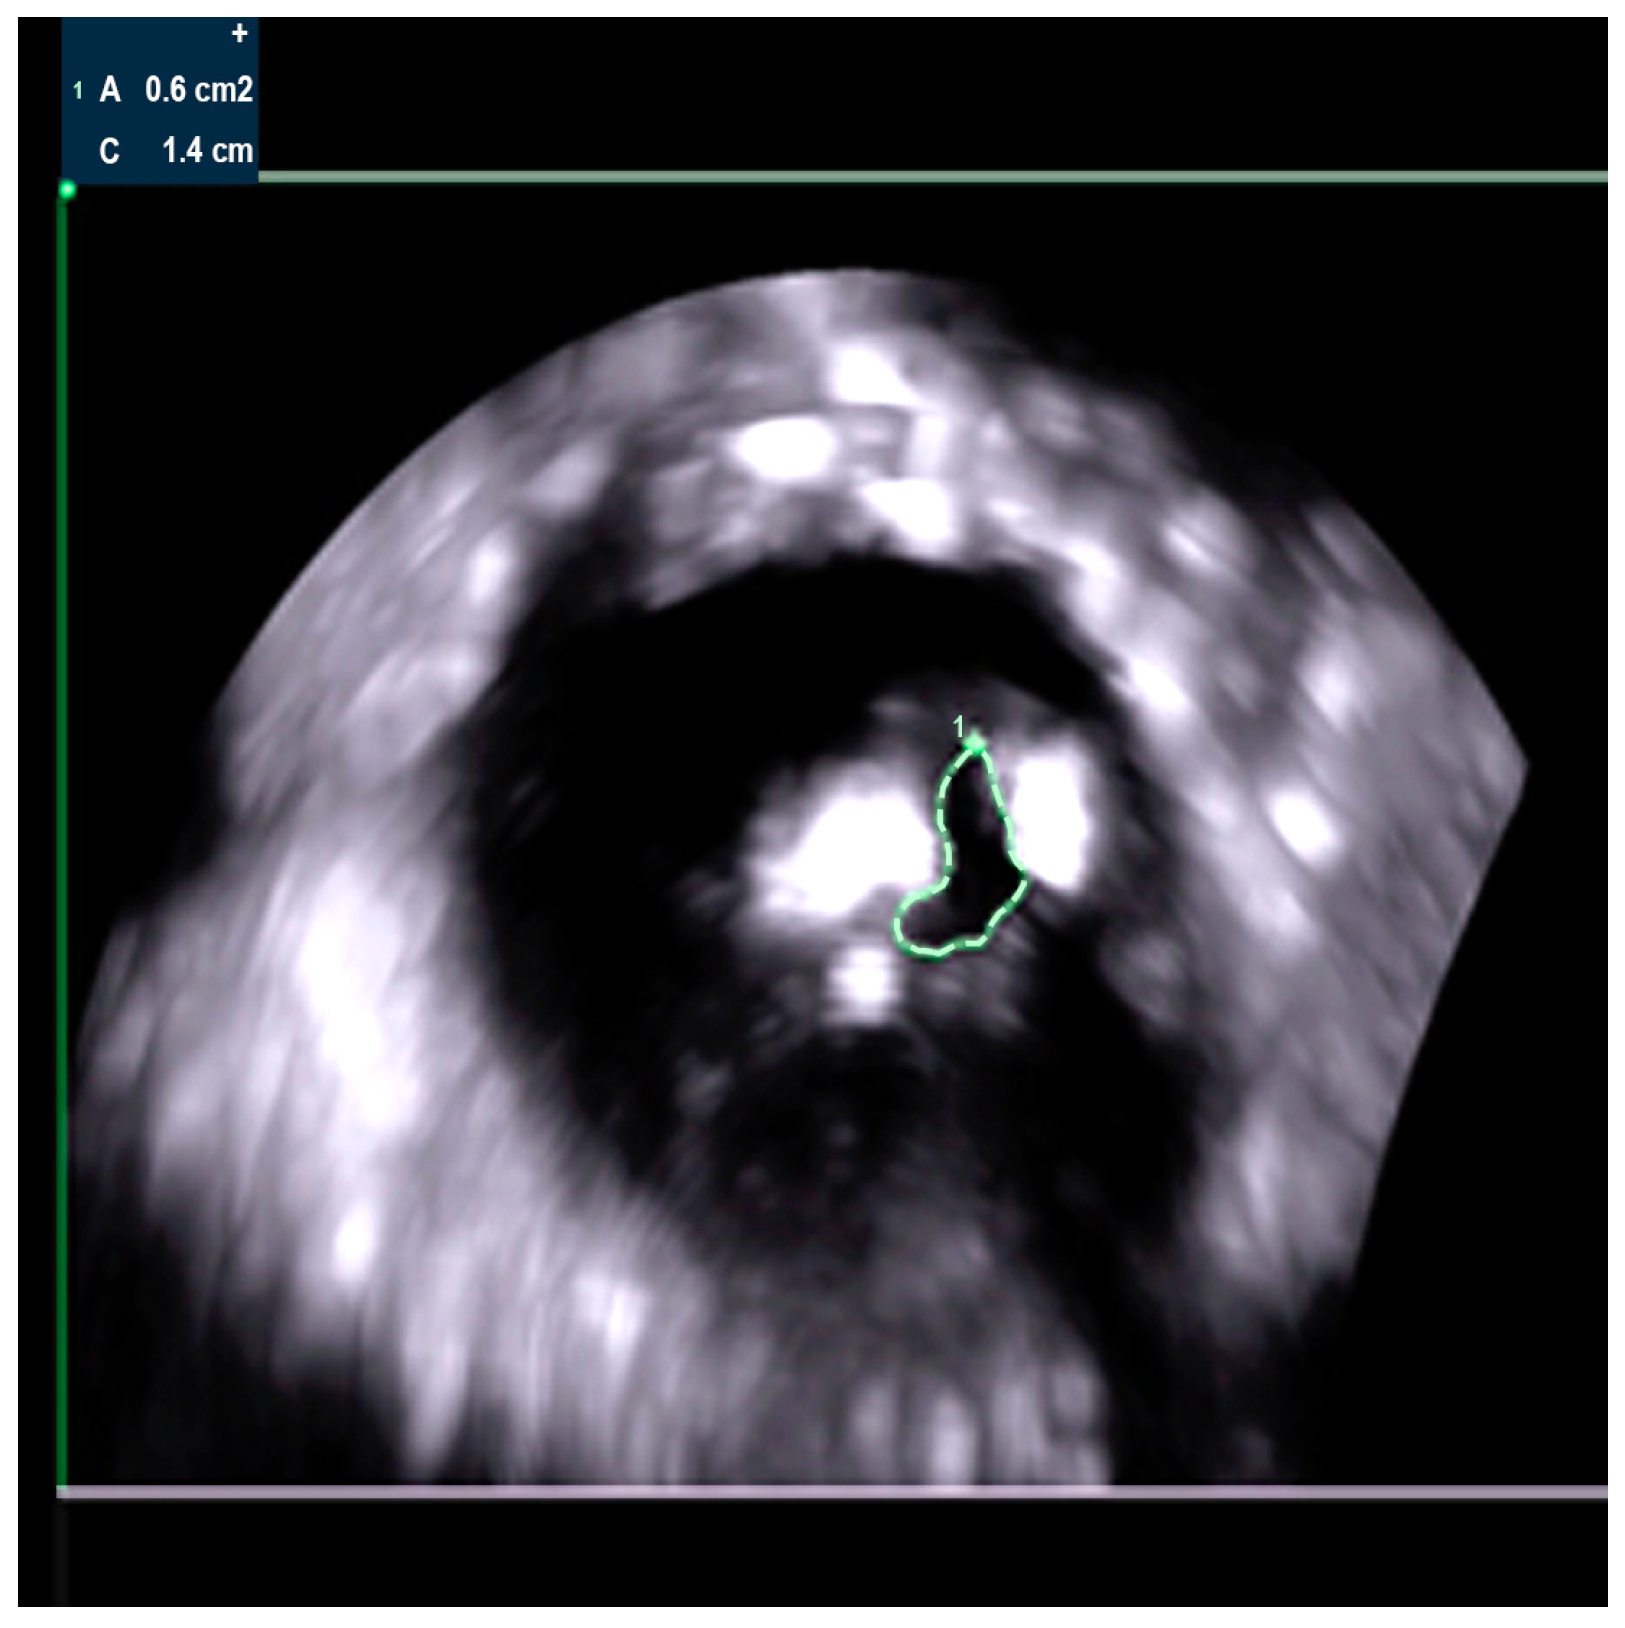

2. Case Presentation